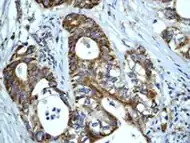

Human Hsp60, the product of the HSPD1 gene, is a Group I mitochondrial chaperonin, phylogenetically related to bacterial GroEL. Recently, the presence of Hsp60 outside the mitochondria and outside the cell, e.g. in circulating blood, has been reported [1], [2]. Although it is assumed that Hsp60 extra-mitochondrial molecule is identical to the mitochondrial one, this has not yet been fully elucidated. Despite the increasing amount of experimental evidences showing Hsp60 outside the cell, it is not yet clear how general this process is and what are the mechanisms responsible for Hsp60 translocation outside the cell. Neither of these questions has been definitively answered, whereas there is some information regarding extracellular Hsp70. This chaperone was also classically regarded as an intracellular protein like Hsp60, but in the last few years considerable evidences showed its pericellular and extracellular residence

HSP60 has been shown to influence apoptosis in tumor cells which seems to be associated with a change in expression levels. There is some inconsistency in that some research shows a positive expression while other research shows a negative expression, and it seems to depend on the type of cancer. There are different hypotheses to explain the effects of positive versus negative expression. Positive expression seems to inhibit “apoptotic and necrotic cell death” while negative expression is thought to play a part “in activation of apoptosis”.[23][24]

As well as influencing apoptosis, HSP60 changes in expression level have been shown to be “useful new biomarkers for diagnostic and prognostic purposes.” [23] According to Lebret et al., a loss of HSP60 expression “indicates a poor prognosis and the risk of developing tumor infiltration” specifically with bladder carcinomas, but that does not necessarily hold true for other types of cancers.[25] For example, ovarian tumors research has shown that over expression is correlated with a better prognosis while a decreased expression is correlated with an aggressive tumor.[25] All this research indicates that it may be possible for HSP60 expression to be used in predicting survival for certain types of cancer and therefore may be able to identify patients who could benefit from certain treatments.[24]